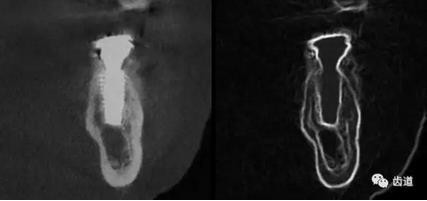

一)牙體牙髓病科

CBCT在牙體牙髓病科治療中,對牙根周圍的解剖關(guān)系、炎癥病變、囊腫等就能夠輕而易舉的進行診斷。甚至與牙齒內(nèi)根管的數(shù)目、走向、分支等都能夠通過牙科CT進行展示,使臨床醫(yī)生的根管治療不再是完全憑手感的“經(jīng)驗科學(xué)”。通過CBCT,還可以對一些“久治不愈“的疑難病例進行檢查和診斷,例如根縱列的診斷、根管內(nèi)異物的定位等,找準(zhǔn)了原因,結(jié)合先進的治療技術(shù)因病施治,使疑難病例的治療變的輕松起來。

1)根管治療中牙膠尖充填在CBCT中的影像

2)根管測量